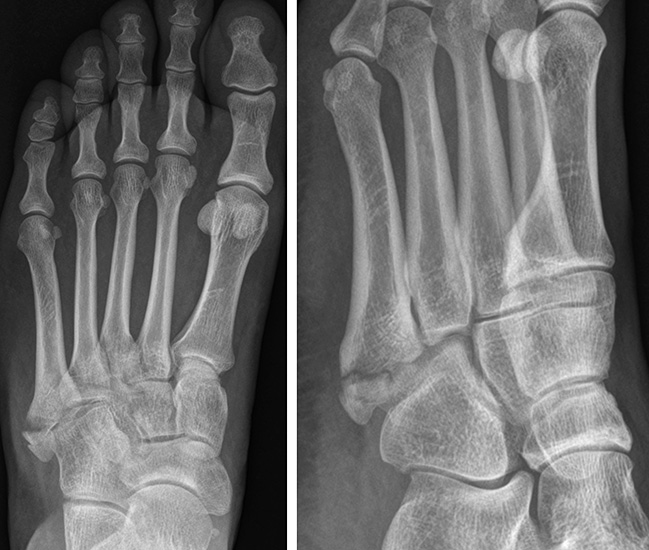

Die in der Literatur am häufigsten verwendete Klassifikation ist die 1993 publizierte, anatomische Klassifikation von Lawrence und Botte 6. Diese basiert auf einer retrospektiven Fallserie und unterscheidet drei Frakturzonen (Abb. 1).

Zone II befindet sich auf Höhe der Articulatio zwischen MT IV und V. Die Zone I liegt proximal, die Zone III distal davon. Interessanterweise vermischen Lawrence und Botte Unfallmechanismen (Avulsionsfraktur/Stressfraktur) und deskriptive Terminologie (Jones’ Fraktur) in ihrer Klassifikation. Eine Vereinfachung dieser Klassifikation publizierten Polzer et al. 2012 7. Basierend auf den Ergebnissen von sechs prospektiven Behandlungsstudien (systematische Literaturrecherche), schlussfolgerten die Autoren, dass Lawrence und Botte Zone I und II Frakturen zusammengefasst werden könnten (Metaphysäre Frakturen). Zone III Frakturen werden als Meta-Diaphysär beschrieben.